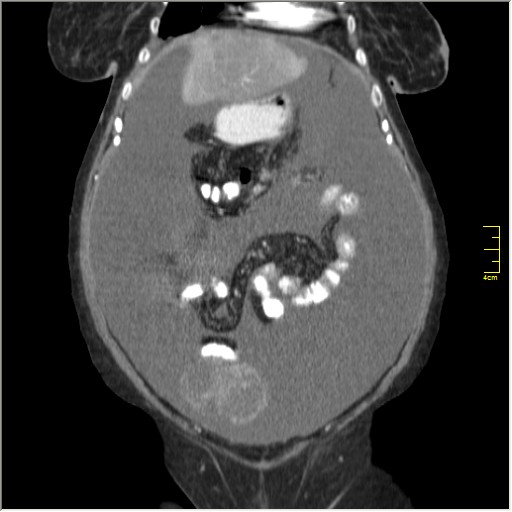

Женщина 72 года. Поступила с жалобами на вздутие живота. После осмотра хирургом, была сразу направлена на КТ брюшной полости.

Итак, асцит с объёмным образованием таза. В данном случае можно быть более конкретным, у пациентки неоплазия правого яичника с региональной лимфаденопатией (увидели?) и выраженным асцитом, характерным именно для злокачественных опухолей яичников. Пациентка оперирована ( операция Вертгейма); диагноз верифицирован: аденокарцинома правого яичника (серозная). Направлена к онкологу для дальнейшего лечения.